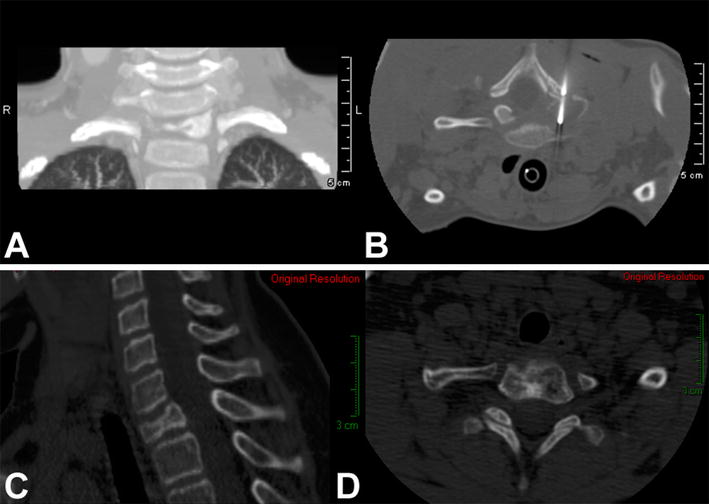

a Anteroposterior radiograph of the pelvis of a 6-year-old boy with a painful osteolytic lesion at the left ischial ramus. CT-guided frozen section biopsy showed eosinophilic granuloma; intralesional methylprednisolone injection was performed. b Anteroposterior radiograph of the pelvis shows complete reconstitution of the lesion 1 year after diagnosis and treatment